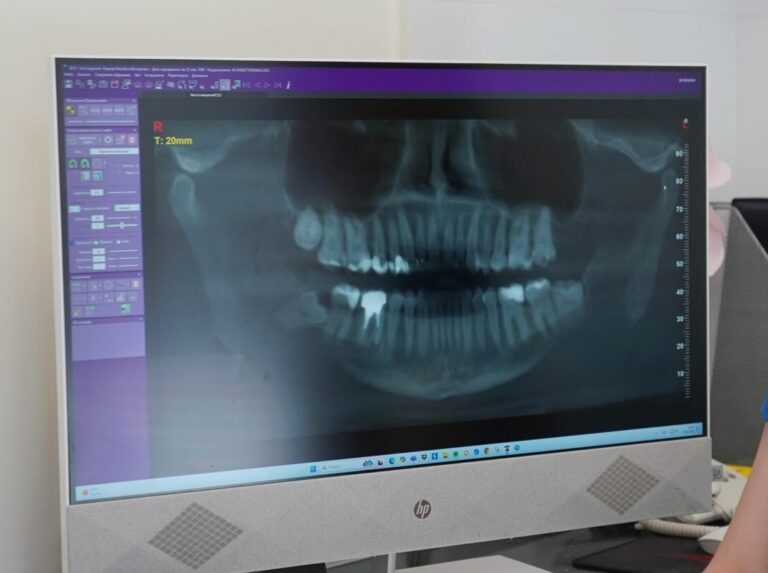

Панорамний знімок зубів (ортопантомограма) — це сучасний метод рентген-діагностики, який дозволяє отримати повне зображення обох щелеп, зубів, коренів і навколишніх тканин. Такий знімок допомагає лікарю оцінити загальний стан ротової порожнини та виявити приховані патології.

Щоб стоматологічні маніпуляції пройшли ефективно, особливо при плануванні складних процедур потрібно отримати повну оглядову картину зубощелепної системи. Досягається це за допомогою ортопантомограми, яка виявляє необхідні стоматологу дані про явні та приховані проблеми ротової порожнини.

Панорамний знімок широко використовується перед видаленням зубів, встановленням імплантів, ортодонтичним лікуванням та при підозрі на запальні процеси. Він дозволяє виявити кісти, гранульоми, прихований карієс та інші проблеми, які неможливо побачити без рентгену.